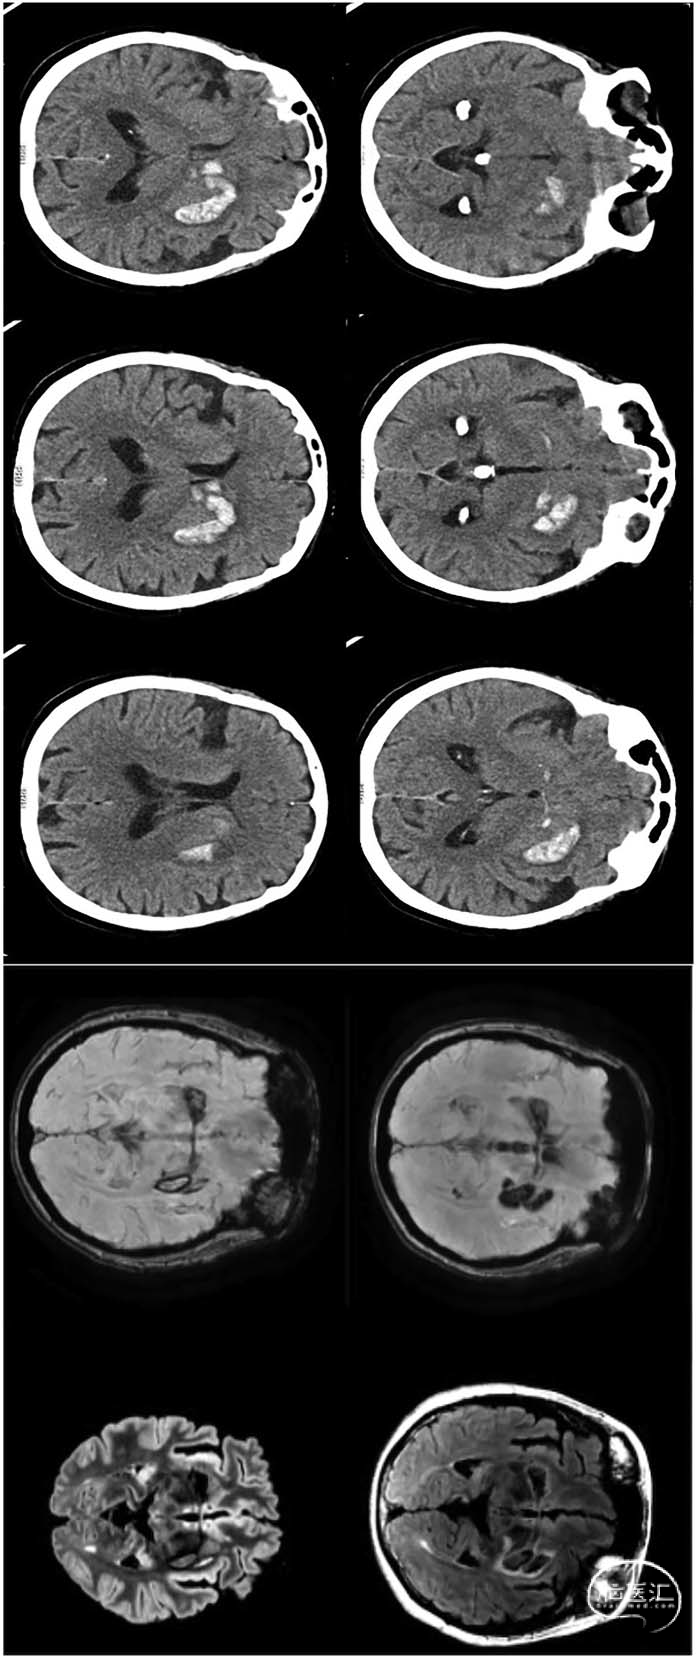

颅脑CT与MRI影像(见图)显示左侧基底节区深部脑出血,出血经Gratiolet管向前跨胼胝体延伸至对侧基底节。

图.入院时颅脑CT轴位图像与3个月后随访MRI(含T2-FLAIR及磁敏感加权血管成像序列)。影像显示左侧基底节区深部脑出血,经Gratiolet管跨胼胝体延伸至对侧基底节区:

深部脑出血经Gratiolet管形成跨胼胝体延伸是一种罕见影像学表现¹,迄今仅见少量病例报道²。这种情况具有显著功能学意义,因其破坏半球间联络功能,可能导致双侧锥体外系运动通路功能障碍及反常运动现象。例如出血同侧出现肌张力障碍,可能源于对侧锥体外系运动回路去抑制,或胼胝体连接中断导致精细运动调节功能受损,最终引发大脑半球间功能失衡。